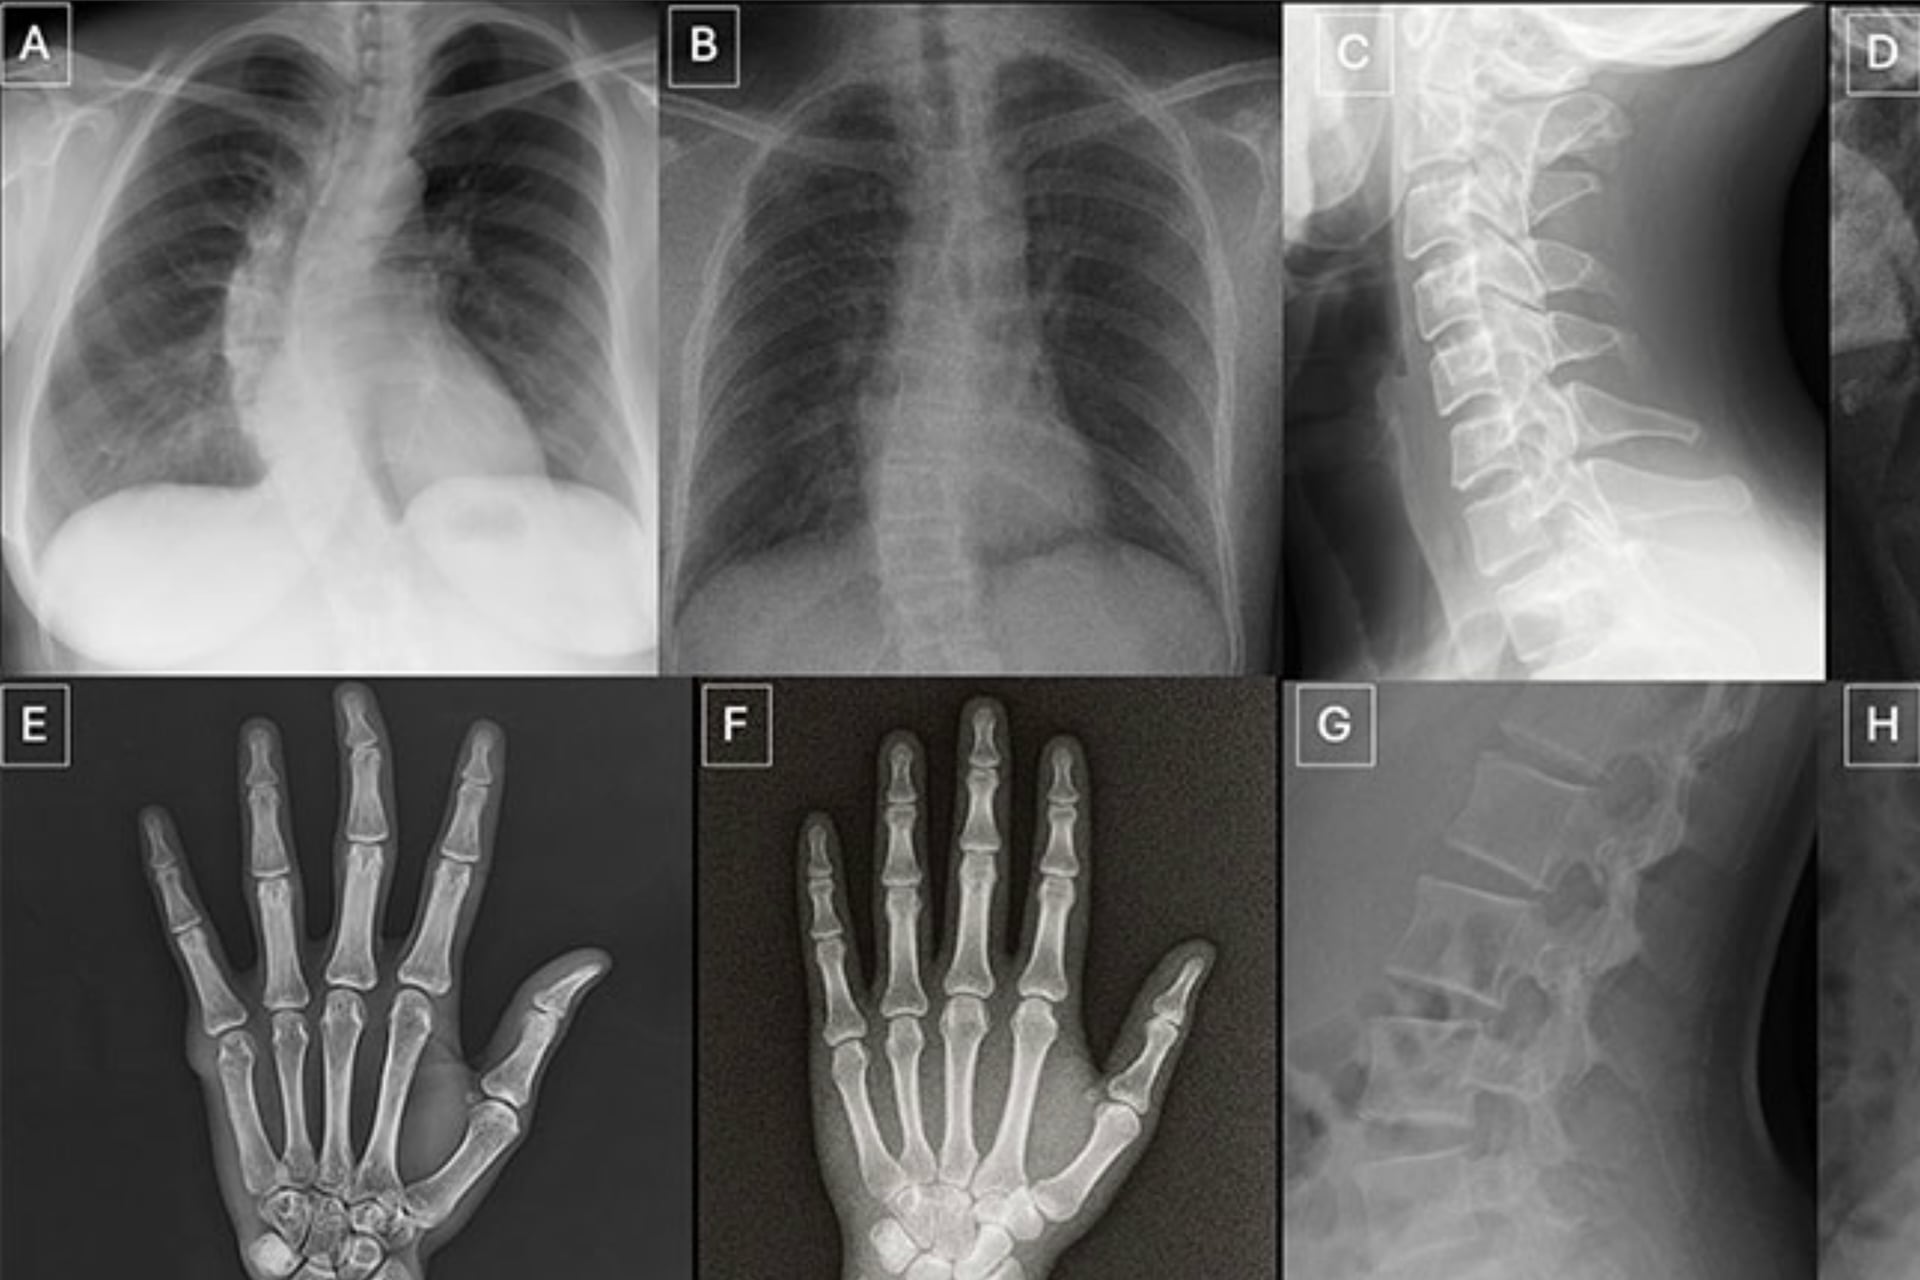

The researchers subjected a group of volunteers, 17 practicing radiologists from six countries, to tests that required them to distinguish real X-rays from AI-generated simulacra across a pool of 264 unique images. The results did not inspire confidence.

The 17 volunteer radiologists that Tordjman’s team tested were exposed to two distinct datasets for this study, published Tuesday in the journal Radiology. The first asked volunteers to look at 154 static X-rays, half genuine radiographs and half Chat GPT-4o-generated forgeries (77 each). The second test utilized a specialized diffusion model AI trained to make believable chest radiographs, with organs like the heart and lungs visible, called RoentGen; volunteers were asked to sort through a dataset of 110 images, 55 real and 55 fake.

Tordjman said he hopes future work will build off these findings to establish educational datasets and detection tools. “Deepfake medical images often look too perfect,” he noted. “Bones are overly smooth, spines unnaturally straight, lungs overly symmetrical, blood vessel patterns excessively uniform, and fractures appear unusually clean and consistent.”